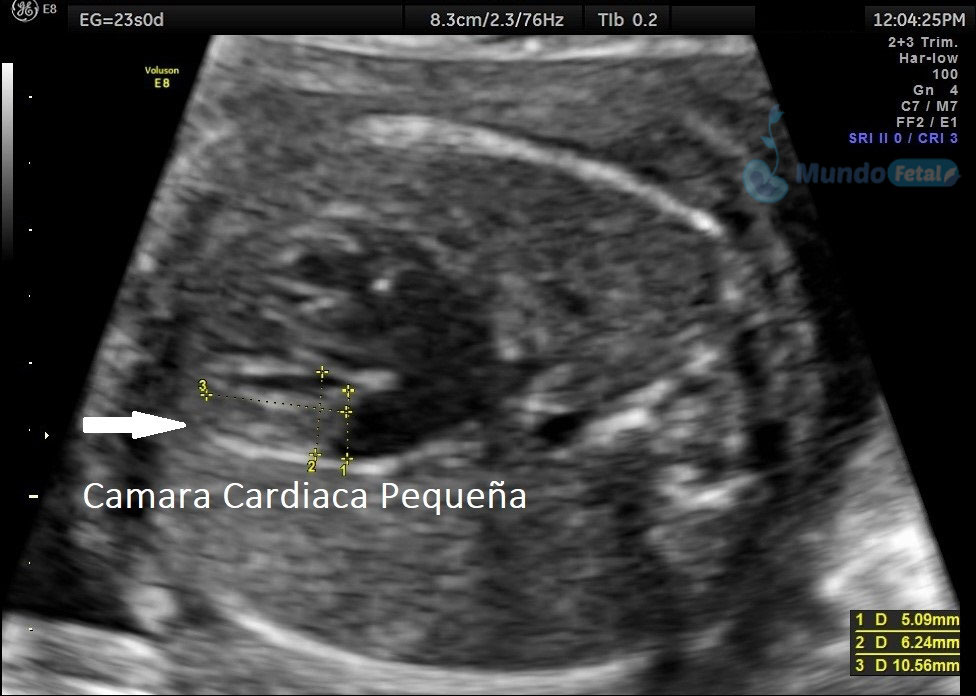

Estudio llevado a cabo en todo bebe, en quien se haya detectado alguna alteración anatómica o marcador de riesgo, valorando todos sus órganos, aparatos y sistemas, de manera específica y detallada.